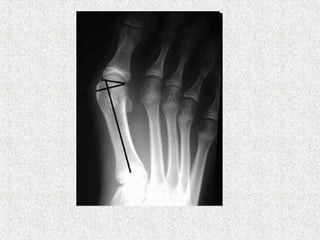

HALLUX VALGUS ANGLE

Normal <15

Mild <20

Moderate 20-40

Severe >40

1st

/2nd

Inter Metatarsal Angle (IMA)

Normal <9

Mild <11

Moderate 11-16

Severe >16